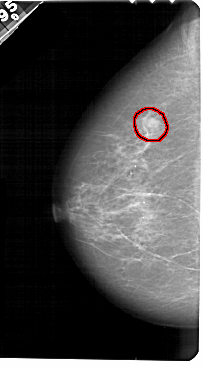

A_1442_1.RIGHT_CC

RIGHT_CC LINES 5251 PIXELS_PER_LINE 2776 BITS_PER_PIXEL 12 RESOLUTION 43.5 NON_OVERLAY

FILE: A_1442_1.LEFT_CC.OVERLAY

TOTAL_ABNORMALITIES 1

ABNORMALITY 1

LESION_TYPE MASS SHAPE OVAL MARGINS ILL_DEFINED

ASSESSMENT 4

SUBTLETY 3

PATHOLOGY BENIGN

TOTAL_OUTLINES 1

BOUNDARY